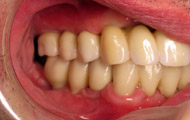

Exemple d’une réhabilitation complète implantaire

Situation clinique initiale

Situation clinique terminée